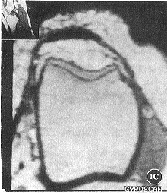

图1A 关节镜下正常髌股关节面 B,C 3D-Volume-FFE-T1WI,MPR像, 关节软骨主体呈高、低、高信号的平行三层结构,表面光滑

2.1 关节镜下32个髌股关节共发现78个正常软骨面,呈白色或乳白色, 表面非常光滑,质地稍硬,其厚度 随部位和年龄不同而异(图1A)关节镜下软骨损伤部位及分 级见表1。

2.2 3D-Volume-FFE T1WI矢状位原始图像及横断位MPR图像正常髌软 骨由表及里呈高、低、高信号的平行三层结构,表面光滑,底层钙化软骨层呈线状低信号分 隔软骨和软骨下骨质(图1B)。股骨滑车软骨呈与髌软骨类似的MRI表现(图1C),仅厚度略薄 ,其中10个滑 车面软骨均匀一致变薄,信号分层特点不明显,但表面仍光滑,关节镜证实为正常软骨面。 FFE T1WI关节软骨MRI表现类似3D-Volume-FFE T1WI,但信噪比稍差,本组5例髌上囊积 液用该序列扫描,软骨与液体界面不能区分。SE-T1WI关节软骨呈高于骨皮质而低于骨髓 的中等信号,信噪比差,信号分层特点不明显,软骨与关节液界面不能确定。各序列软骨损 伤 MRI分级与关节镜分级对照见表2~4(图2~4)。